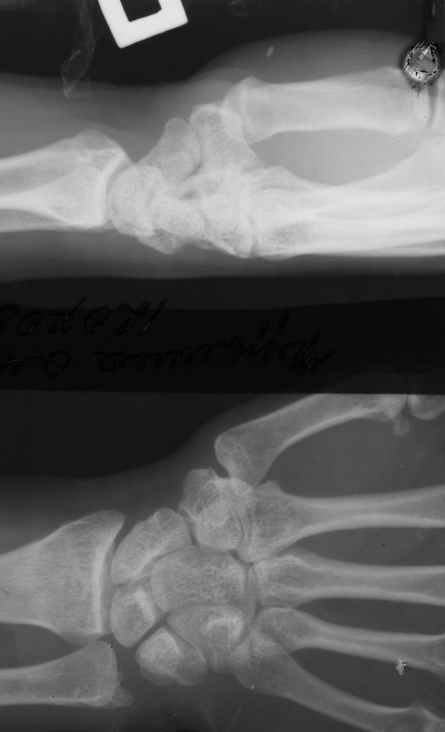

Диагноз на 15.07.05: Стойкая смешанная дермотеногенная контрактура 3,4 пальца правой кисти 3 степени.

Диагноз: Стойкая Смешанная дермотеногенная контрактура 3,4 пальца правой кисти.

Судя по выписному эпикризу, рентгенограммам и фотографиям, пациенту

показано этапное лечение.

К сожалению, мне непонятна локализация кадра

(прилагаю).

Это 3 или 4 межпальцевой промежуток? Гранулирующая рана или свищ?

Есть ли отделяемое в зоне тенара?